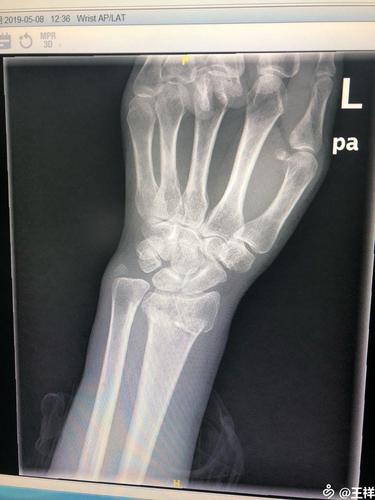

左桡骨远端粉碎性骨折修复术

找一个园子里的正位片,对照一下尺桡骨远端的大致关系.